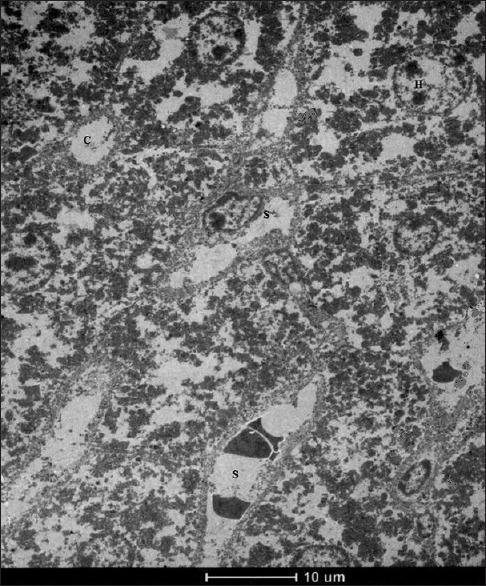

Ultrastructural Alterations of Liver Tissue Cells in Methotrexate-Treated Balb/c Mice.

Ultrastructural changes in rat livers perfused in vitro and in vivo with a high dose of methotrexate.

Hepatic ultrastructure in leukemic children treated with methotrexate and 6-mercaptopurine.

Cytoprotective effects of molsidomine against methotrexate-induced hepatotoxicity: an experimental rat study.